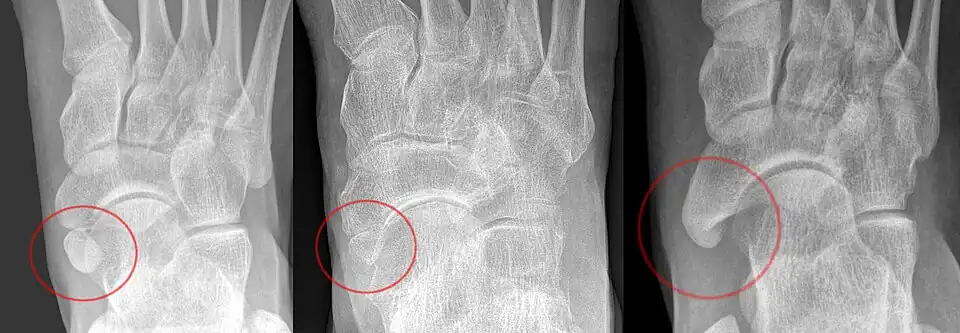

The Geist classification divides the accessory navicular bones into three types.[3]

• Type 1: An os tibiale externum is a 2–3 mm sesamoid bone in the distal posterior tibialis tendon. Usually asymptomatic.

• Type 2: Triangular or heart-shaped ossicle measuring up to 12 mm, which represents a secondary ossification center connected to the navicular tuberosity by a 1–2 mm layer of fibrocartilage or hyaline cartilage. Portions of the posterior tibialis tendon sometimes insert onto the accessory ossicle, which can cause dysfunction, and therefore, symptoms.

• Type 3: A cornuate navicular bone represents an enlarged navicular tuberosity, which may represent a fused Type 2 accessory bone. Occasionally symptomatic due to bunion formation.